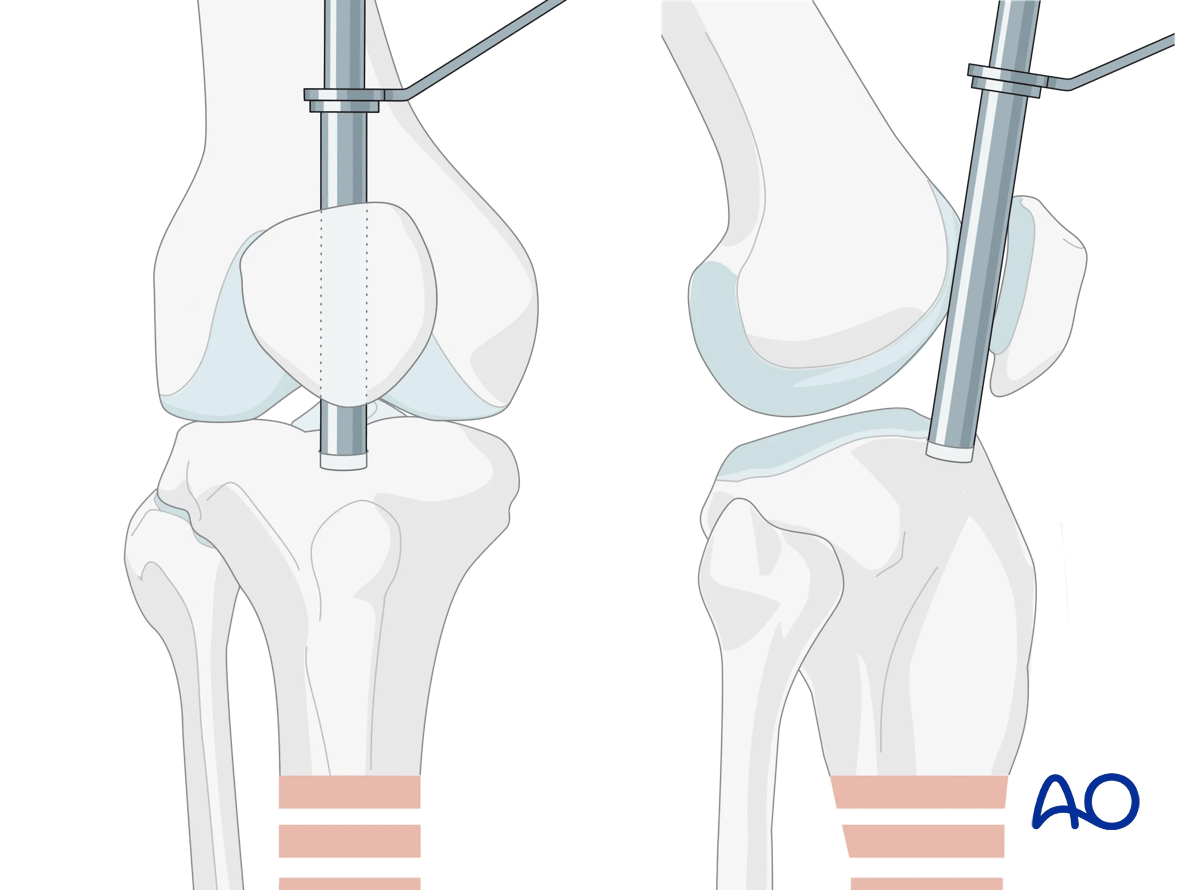

Obtaining appropriate fluoroscopic views of the proximal tibia

It is imperative to obtain appropriate AP and lateral views of the proximal tibia to ensure that the proper entry site for the tibial nail is obtained. A proper AP view has the lateral border of the tibial plateau bisect the fibular head. A proper lateral view has the femoral condyles superimposed on each other. The entry point for a tibial nail on the lateral view should be at the anterior edge of the joint line and on the medial aspect of the lateral tibial spine on the AP view.

Suprapatellar intramedullary nailing, Obtaining appropriate fluoroscopic views of the proximal tibia